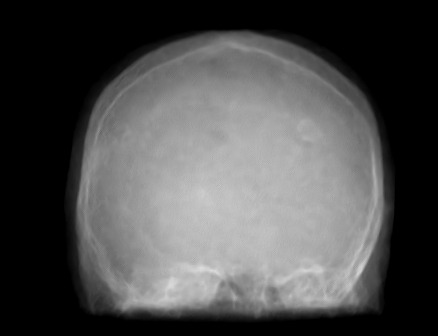

III-A Data

We analyze the performance of the proposed approach based on 21 pairs of clinical patient head datasets. First, 8 pairs of tomographic T1 and T2 Flair MRI datasets (256x 256256x256256\;\text{x}\;256) are used. Second, cone-beam X-ray and MRI projection images (512x 512512x512512\;\text{x}\;512) generated from 13 patients are utilized (MR: 1.5 T MAGNETOM Aera / CT: SOMATON Definition, Siemens Healthineers, Erlangen / Forchheim, Germany). Two pairs of patient dataset of each modality were reserved for validation and testing. Image registration of the corresponding datasets is performed using 3D Slicer [30]. The forward projections are based on the work of hybrid MR/X-ray imaging by [31, 32, 33] and are created with the CONRAD framework [34]. 108 projections are created per patient that are distributed equiangularly along the azimuthal and in 60 degree range along the inclination angle. Note that the type of data presented here is only to be seen as an example. The proposed approach is not tailored to any particular data type or combination of data types.

For the task of super resolution, low-resolution images are created by nearest neighbor downsampling by a factor of 4. For denoising, noisy images are generated from the ground truth by applying Poisson noise. Both methods are only an approximation of the real physical processes. In MRI, for example, the resolution and the signal-to-noise ratio are directly related [35]. Also, noise in X-ray imaging is not just Poisson noise but a combination of multiple sources of noise [36]. For detailed investigations on a specific problem area a corresponding simulation should therefore be conducted.

Figure 2: Inputs and outputs of the guided filtering pipeline based on the WDSR network. T1 & T2 MRI pairs (a)-(e) and CT & MRI projection images (f)-(j).